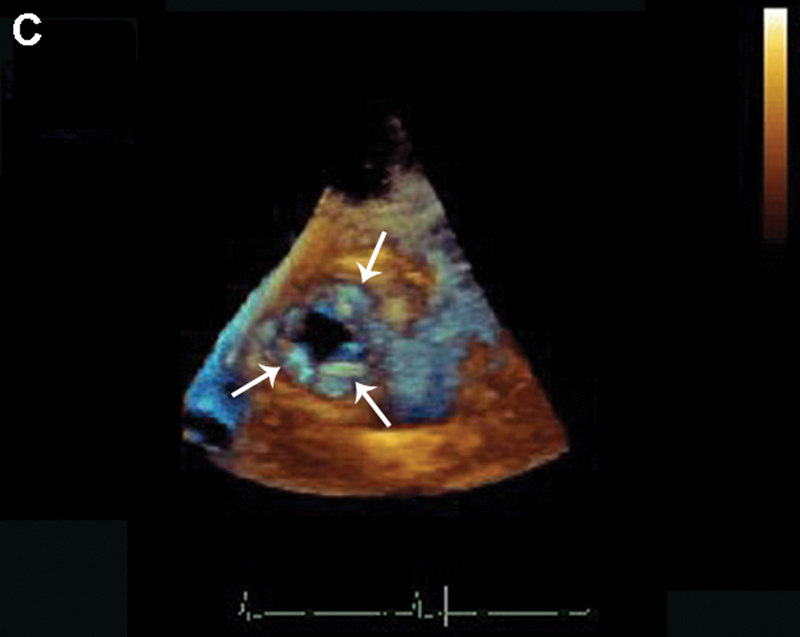

فحوصات تشخيصية لبعض امراض القلب والشرايين التاجية